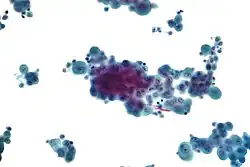

Anteroposterior chest X-ray of a pleural effusion. The A arrow shows fluid layering in the right pleural cavity. The B arrow shows the normal width of the lung in the cavity.

When a pleural effusion has been determined to be exudative, additional evaluation is needed to determine its cause, and amylase, glucose, pH and cell counts should be measured.

• Red blood cell counts are elevated in cases of bloody effusions (for example after heart surgery or hemothorax from incomplete evacuation of blood).

• Amylase levels are elevated in cases of esophageal rupture, pancreatic pleural effusion, or cancer.

• Glucose is decreased with cancer, bacterial infections, or rheumatoid pleuritis.

• pH is low in empyema (<7.2) and maybe low in cancer.

• If cancer is suspected, the pleural fluid is sent for cytology. If cytology is negative, and cancer is still suspected, either a thoracoscopy, or needle biopsy[6] of the pleura may be performed.

• Gram staining and culture should also be done.

• If tuberculosis is possible, examination for Mycobacterium tuberculosis (either a Ziehl–Neelsen or Kinyoun stain, and mycobacterial cultures) should be done. A polymerase chain reaction for tuberculous DNA may be done, or adenosine deaminase or interferon gamma levels may also be checked.